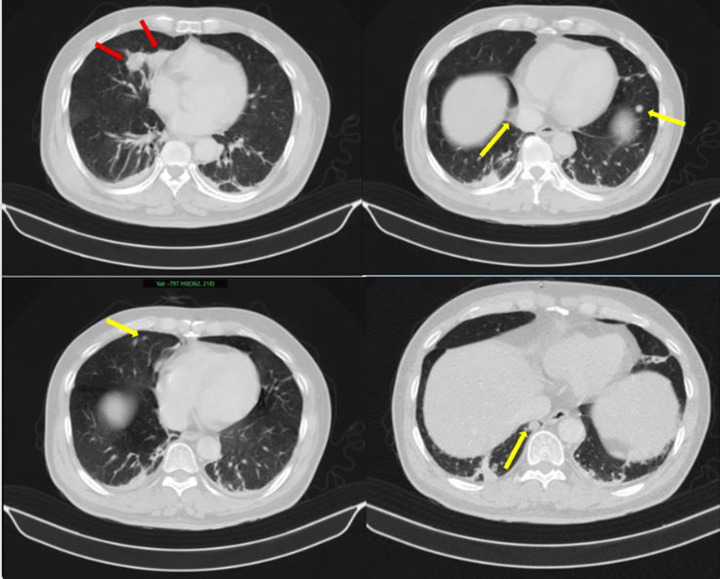

Những hình ảnh bất thường trên phổi của bệnh nhân (Ảnh: BV Bạch Mai)

Thách thức lớn nhất trong trường hợp này là xác định bản chất các tổn thương: đâu là khối u nguyên phát, đâu là di căn. Nếu chẩn đoán không chính xác, việc lựa chọn phương pháp điều trị có thể sai lệch, ảnh hưởng trực tiếp đến hiệu quả điều trị.

Kết quả sinh thiết và phân tích mô bệnh học kết hợp hóa mô miễn dịch giúp làm rõ: khối u phổi là ung thư biểu mô tuyến của phổi, trong khi khối u tuyến tiền liệt là ung thư biểu mô tuyến với điểm Gleason 9 - thuộc nhóm nguy cơ cao. Hai loại ung thư này có nguồn gốc hoàn toàn khác nhau, không phải di căn chéo.